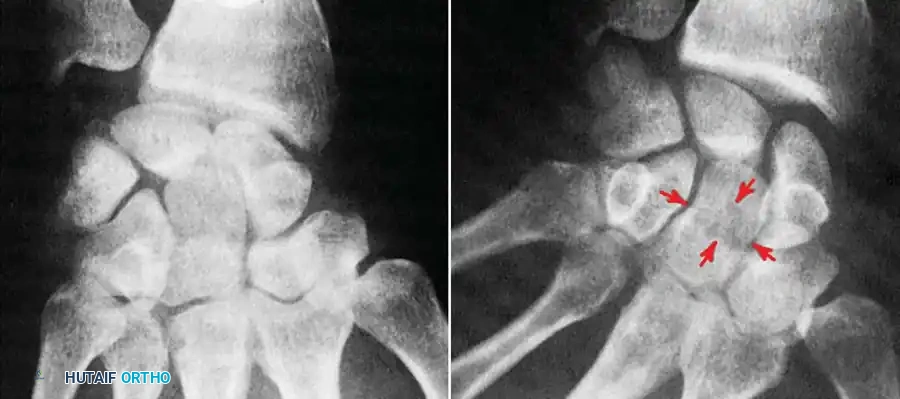

1. Posteroanterior (PA) View: Evaluates Gilula’s three carpal arcs. Disruption of these arcs indicates carpal instability or fracture.

Instability Series and Dynamic Imaging

If standard radiographs are normal but ligamentous instability is clinically suspected, an instability series is mandatory. This includes:

* Anteroposterior clenched-fist views (to dynamically widen the scapholunate interval, >3mm indicates a Terry Thomas sign).

* PA views in maximum radial and ulnar deviation.

* Lateral views in full flexion and extension.